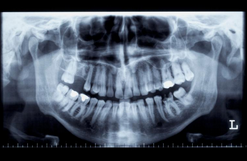

- 치과 의사와의 상담 및 검사: 치과 의사와의 상담을 통해 환자의 상태와 필요한 수술 범위 등을 확인합니다. 검사를 통해 치아와 관련된 질병이나 문제를 파악할 수 있습니다.

- 수술 계획 및 준비: 검사 결과를 바탕으로 수술 계획을 수립하고, 환자의 건강 상태와 약물 복용 여부 등을 확인합니다. 수술 전에는 국소마취나 전신마취 등의 마취 방법을 결정하고, 필요한 경우 항생제 등의 약물을 처방합니다.